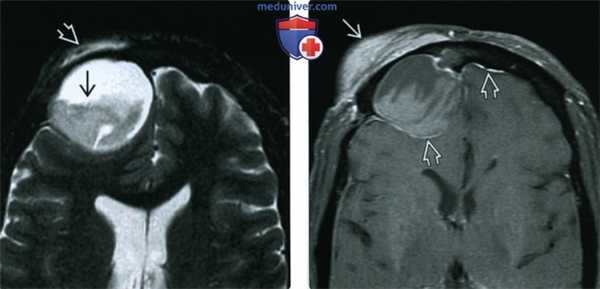

(Слева) При аксиальной МРТ Т2 FS визуализируется большое мукоцеле правой лобной пазухи с содержимым вариабельной интенсивности в нижних отделах. Мукоцеле распространяется в поверхностные мягкие ткани, приводя к их отеку.

(Справа) При аксиальной МРТ Т1 C+ FS у пациента с лобным мукоцеле: определяется отек и контрастное усиление поверхностных мягких тканей над разорвавшимся мукоцеле. Определяется также дуральное контрастирование передней черепной ямки, сопоставимое с ранним воспалением оболочек мозга.